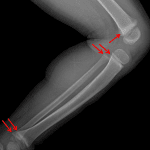

Indication: Leg pain

Findings

- No acute fracture or malalignment

- Dense bands in the distal femoral and proximal and distal tibial and fibular metaphyses

Diagnosis

- Lead poisoning

No acute fracture or malalignment.

Dense metaphyseal bands, which can be a normal variant or can be seen with chronic illness, lead poisoning, or as a medication effect.